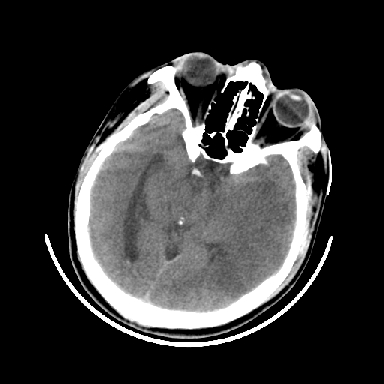

以下是引用dyqct在2007-4-9 11:18:00的发言:[br]左额颞顶叶、基底节区呈大片低密度区,累及皮质,中度占位效应,同侧侧脑室旁见小片状高密度区,边界清楚。中线结构向右弧形移位。右侧侧脑室略扩张。[br]考虑:1、左侧额颞顶叶、基底节区缺血性脑梗塞(符合大脑中动脉供血区)伴出血。[br] 2、建议增强扫描进一步检查。

以下是引用卜一在2007-4-9 15:08:00的发言:[br][br] 左侧额颞顶叶、基底节区缺血性脑梗塞(符合大脑中动脉供血区)伴出血。原因:多考虑外伤后出血,形成血栓所致。 [br]